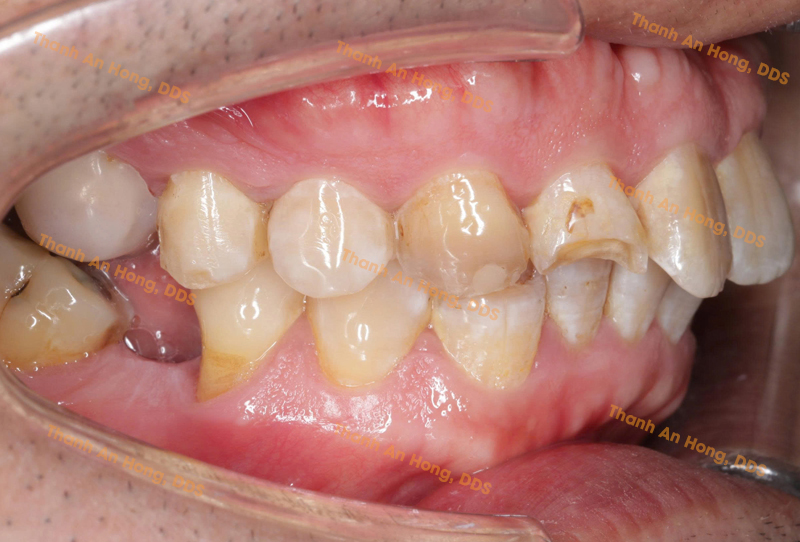

HÌNH ẢNH THỰC TẾ

Chỉnh mắc cài giảm hô